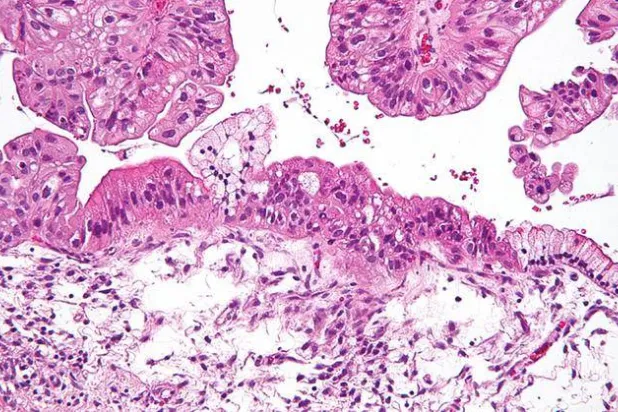

أعلن تقرير لجمعية السرطان الأميركية أن معدلات الإصابة بسرطان القولون والمستقيم ترتفع بسرعة بين الأشخاص في مرحلة العشرينات والثلاثينات والأربعينات.

وجدت دراسة كندية أن دواءً يُستخدم لعلاج الإدمان، يعد وسيلة آمنة للقضاء على الخلايا الجذعية السرطانية في أورام القولون والمستقيم.